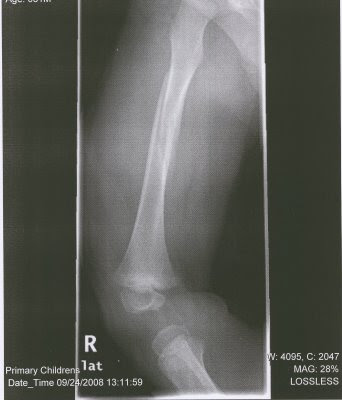

Yesterday was an interesting day to say the least. It started out like any other day. I just finished bathing the boys and they were playing in my room while I was cleaning up the bathroom but then I hear a THUD! Preston and Cooper were fighting over their toy Zebra and Preston told me later, "I jumped off the bed like Superman." He jumped off my bed and broke his femur bone. I didn't know it was broken, but I got us all dressed and went over to my neighbor's house to ask for a second opinion. I knew his leg hurt really bad, but I couldn't tell it was broken. I called Cam and he came over and he made the decision to call the ambulance. We were taken up to Primary Children's Hospital. We spent most of the day in the ER then he was taken into surgery to straighten his leg and have the cast put on. It is the most horrible cast ever. It is on both of his legs and it goes up to his belly button. He will be in it for six weeks. He is so frustrated. I feel so bad for the poor kid!